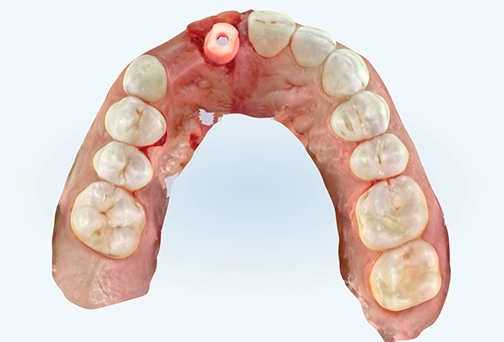

iTero scan taken immediately after implant placement.

Clinically made custom abutment